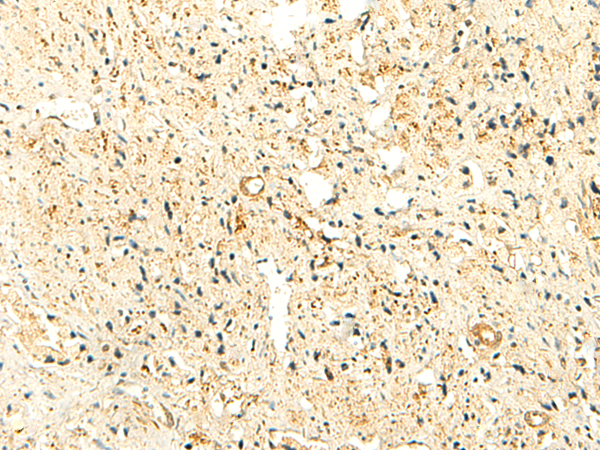

IHC positive control: |

Human tonsil and Human prostate cancer |

IHC Recommend dilution: |

40-200 |